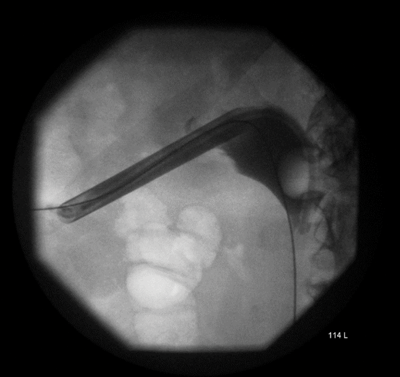

Figure 4.

A percutaneous puncture removed the stent, the radiological nephrostomy tube was removed and a 16F urethral catheter was inserted as a permanent nephrostomy in a patient who was now dialysis dependent (Figure 4). The patient bled post-procedure requiring embolisation (Figure 5).